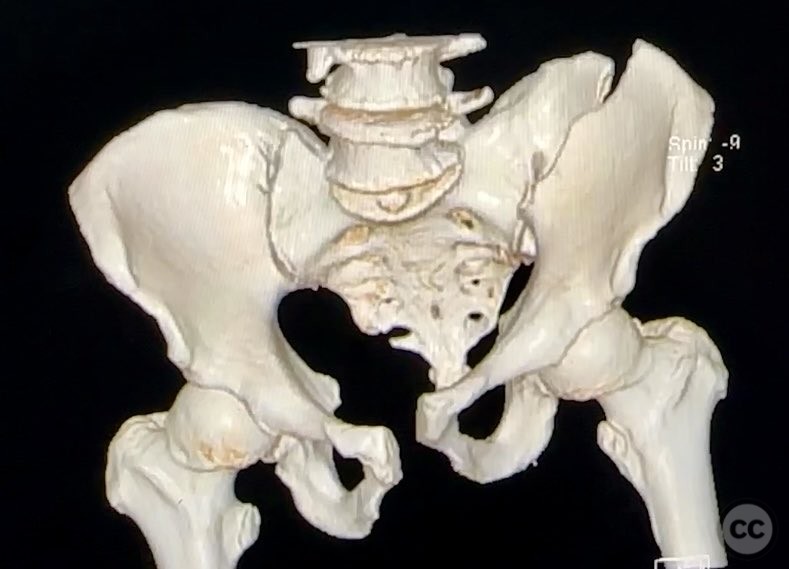

Complete Iliac Fracture with Symphysis Pubis Disruption and Contralateral Incomplete SI/Iliac Fracture

Clinical Details

Clinical and radiological findings:  A patient sustained a high-energy pelvic ring injury characterized by a complete left iliac fracture extending from the iliac crest to the greater sciatic notch, associated with a complete disruption of the symphysis pubis (SP). Additionally, there was a less displaced, incomplete right sacroiliac (SI)/iliac fracture. The injury pattern is consistent with an AO/OTA 61-B2.3 (lateral compression type II) pelvic ring injury. No neurovascular compromise or significant soft tissue injury was reported.

Preoperative Plan

Planning remarks:  The preoperative plan included open reduction and internal fixation of both the iliac fracture and the symphysis pubis disruption. The anatomical approach was planned via direct anterior exposure to the symphysis pubis and an ilioinguinal approach to the iliac wing fracture, with reduction maneuvers at both the iliac crest and pelvic brim.